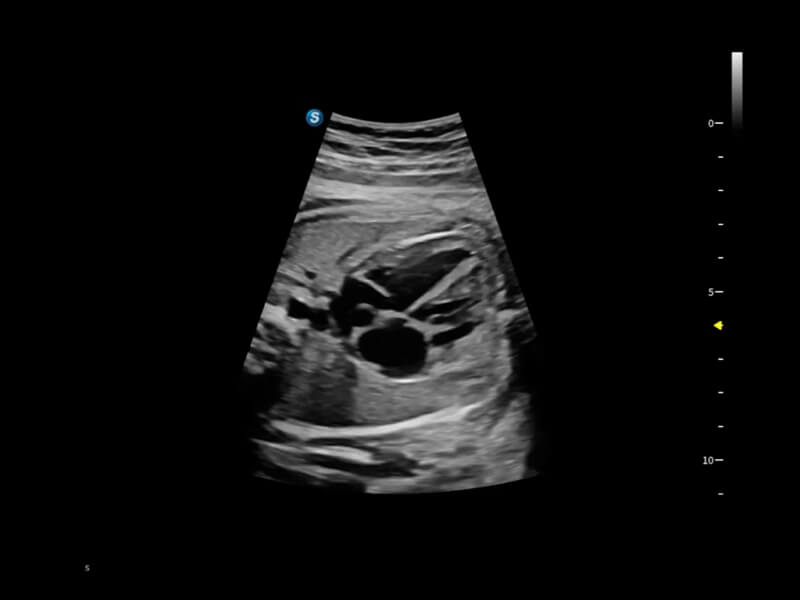

作为开立医疗全新打造的超高端旗舰超声产品,从探头抬起唤醒开启扫查到多维探头发射接收,通过先进的场成像发射、自适应聚合重建等技术,基于RF Data原始射频数据在图像生成、高端功能等方面实现突破,为妇产科、儿科提供全方位临床解决方案。

丰富的血流动力学检测技术,可在不同医疗场景中高效捕捉血流信号,助力临床诊疗。

在传统血流的基础上优化扫查和算法策略,能够更好的抑制组织信息,提炼红细胞运动信息,得到更高帧频,高灵敏度和分辨率的血流信号,还原更真实的血流动力学。